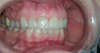

Les dents sont usées et recouvertes de composite, des facettes ont été placées sur 10 dents du haut et 10 dents du bas.

Vue de face en ouverture. On peut observer un réalignement des dents du bas en jouant sur les volumes des facettes.